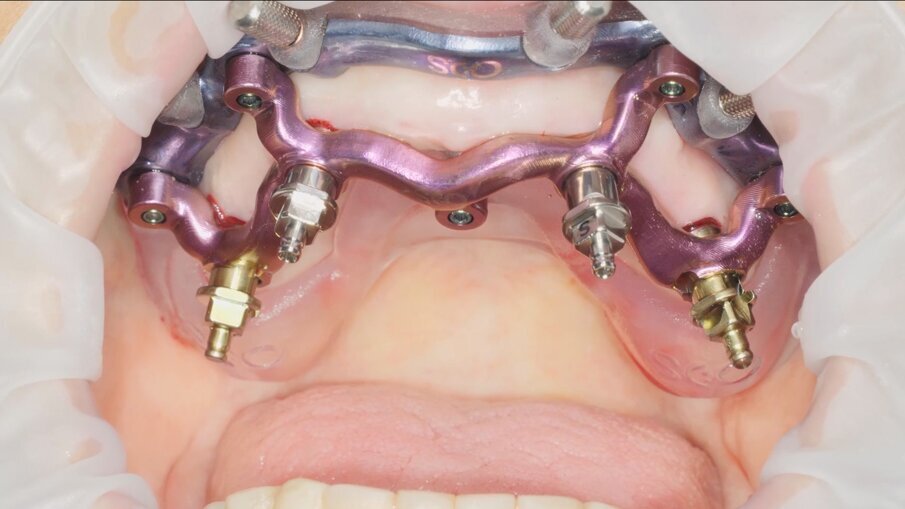

Veniamo quindi al posizionamento della protesi mediante carrier, a sua volta ancorato agli stessi punti di fissaggio della dima base. È significativo osservare come la stabilizzazione della sola vite palatale consenta l’allineamento perfetto tra i sistemi di fissaggio (Fig. 22), mentre il dettaglio mostrato in Fig. 24 illustra efficacemente come prima della cementazione della protesi l’accoppiamento e la centratura del foro protesico appaiano perfetti, confermando quindi come l’obiettivo di alloggiamento della protesi nella sede prestabilita sia stato colto. Per la fase di cementazione con cemento duale si è prestata attenzione alla realizzazione di un foro aggiuntivo per permettere al materiale di raggiungere gli abutment. I fori di accesso alle viti vengono tappati con filo di teflon (Figg. 25, 26) ed è a questo punto possibile andare a fissare la protesi e rimuovere il sistema carrier (Fig. 27). Lasciamo la dima in posizione, così che nell’eventualità in cui un abutment non dovesse essere stato cementato correttamente, ci riserviamo la possibilità di riprendere il posizionamento strategico dell’intero sistema Pcube, intercettando possibili impedimenti alle manovre di finalizzazione del caso.

Nella fase di controllo finale possiamo apprezzare come i rapporti di intercuspidazione programmati siano stati perfettamente rispettati (Fig. 28), senza necessità di ricorrere a procedure di auto-centratura della protesi, grazie ad una attenta pianificazione digitale. Eseguiamo una scansione con scan abutment in posizione prima di procedere con la rimozione della dima base e il fissaggio della protesi (Figg. 29-31). Controlliamo le possibilità di mantenimento igienico tenendo conto che, trattandosi di un intervento flapless, non abbiamo le problematiche legate alla gestione di una linea di incisione (Fig. 32). La Fig. 33 mostra la corretta guarigione dei tessuti quindici giorni dopo il trattamento. Eseguiamo un controllo radiografico mirato a verificare il corretto alloggiamento di tutti gli impianti e della protesi (Fig. 33), dove possiamo vedere la struttura di rinforzo in fibra di vetro.